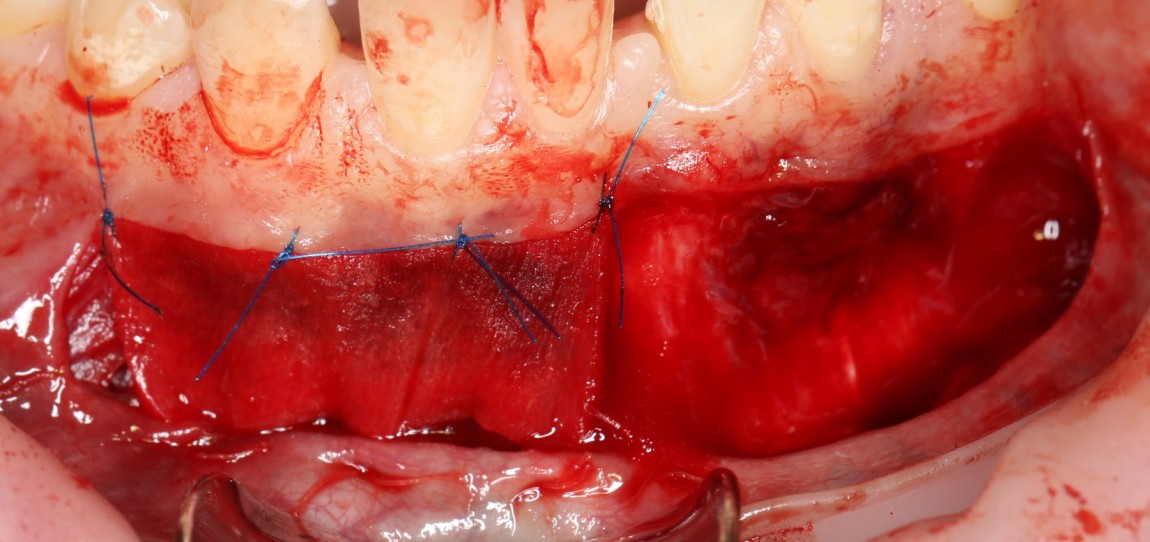

Матрица Mucograft имеет два слоя: наружный плотный и внутренний более рыхлый. Так вот, материал фиксируется швами за наружный плотный слой. В данном случае, я использовал нерезорбируемый шовный материал Prolene 6-0 в верхнем участке раны и Vicrlyl 6-0 — в нижнем:

Вообще, лучше везде фиксировать нерезорбируемым шовным материалом. Просто снятие швов в области будущей переходной складки представляет известные сложности (врастают), и я решил облегчить жизнь пациентке и себе. Но делать так постоянно не рекомендую — использование резорбируемых плетеных шовных материалов, особенно в условиях некачественной гигиены, может привести к образованию лигатурных свищей.

Матрица фиксируется, в первую очередь, к надкостнице, потом тем же вколом подцепляется слизистая оболочка. Получаются вот такие стежки:

Это как раз тот наглядный пример, где показана вся суть хирургии — мы больше шьем, чем режем.))

Операция закончена: